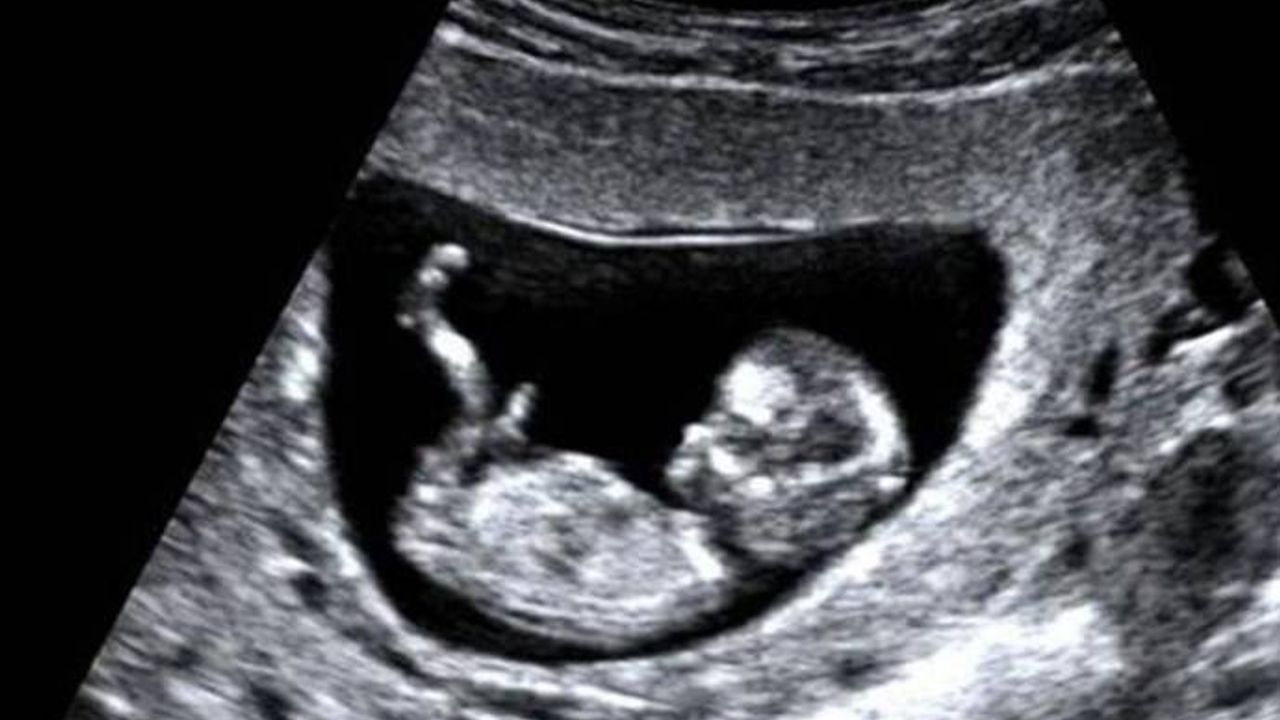

Batman'da hamile eşi ile doktora giden bir kişi, çocuklarının cinsiyetini söyleyen doktoru CİMER'e şikayet etti.

Sözcü yazarı Saygı Öztürk, eşinin talebi olmadan bebeğinin cinsiyetini açıklayan kadın doğum doktorunu CİMER’e şikâyet edilmesini kaleme aldı. Sağlık Bilimleri Üniversitesi Öğretim Üyesi Prof. Dr. Şaban Şimşek’in söz konusu duruma ilişkin yaptığı açıklamada, “Şimdi CİMER yetkilileri ve diğerleri, Cumhurbaşkanlığı adına halkın şikayetlerini alırken ve değerlendirirken nelere yol açtığınızı, bizzat onun adını taşıyan üniversitenin tıp fakültesini ne hale düşürdüğünüzü fark edebiliyor musunuz? Ama kime anlatalım ki? Şimdi kalkıp birisi ‘Onların gözleri var görmezler, kulakları var işitmezler, kalpleri var hissetmezler' dese ne diyebilirsiniz?” ifadelerini kullandı. Doktor Yüksel Işık ise “Cinsiyet karışıklığı şüphesi olabiliyor. Ben de gelen hastama bebeğinin cinsiyeti konusunda bilgi verdim. Bu benim hastaya karşı görevimdir” diye konuştu. 13 yıllık uzman hekim, ilk kez böyle bir şikayetle karşılaştığını ifade etti. CİMER’e yapılan şikâyet ise şöyle: “CİMER başvurusuyla, ... adlı şahıs, ‘Batman Özel Zilan Hastanesi Kadın Doğum Doktoru Yüksel Işık, 11 Eylül 2021 tarihinde, hamile eşimin kontrolünü yaptığı esnada, eşimin talebi olmamasına rağmen çocuğumun cinsiyetini kendisine bildirmiş ve benim hayatımda yaşayabileceğim bu büyük heyecana engel olmuş bu da benim ve eşimin çok üzülmesine, tartışmamıza sebebiyet vermiştir' https://tele1.com.tr/burkina-fasoda-bir-cocuk-sapanla-fransiz-ordusunun-ihasini-dusurdu-512816/